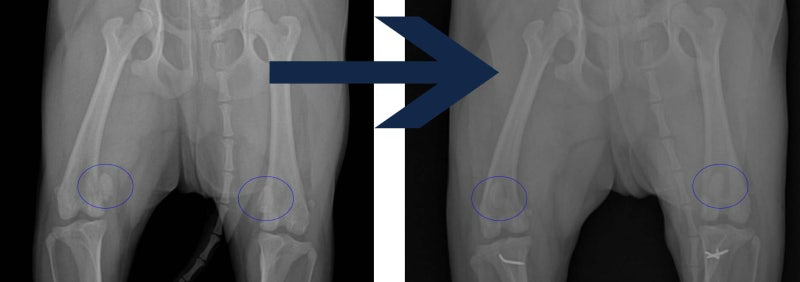

슬개골탈구 수술 전/ 후 x-ray 사진 결과

해당 환자의 수술 전후 x-ray사진입니다. 다리 안쪽으로 돌아가 있던 슬개골이 정상위치로 돌아가있는것을 확인할 수 있습니다. (파란색 동그라미 부분) 슬개골 탈구 수술은 옆으로 돌아간 슬개골을 정상위치로 돌려서 더이상 빠지지 않게 하는 것이 중요하고, 수술을 했어도 무리한 운동이나, 점프하기, 두 발로 일어서기등 관절에 부담이 되는 자세는 좋지 않습니다.

해당환자는 수술 후 한달 뒤에 재검받으러 왔을때, 보행에 이상이 없고 방사선상으로도 문제가 없음을 확인했습니다.